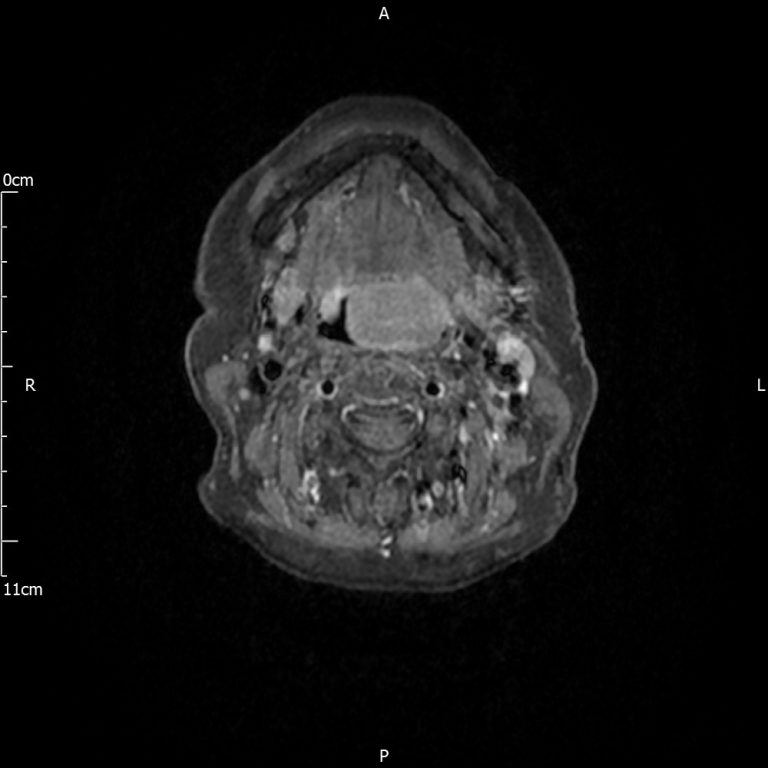

MRI scan of a patient with a large tongue base tumour who noticed a change in their swallowing